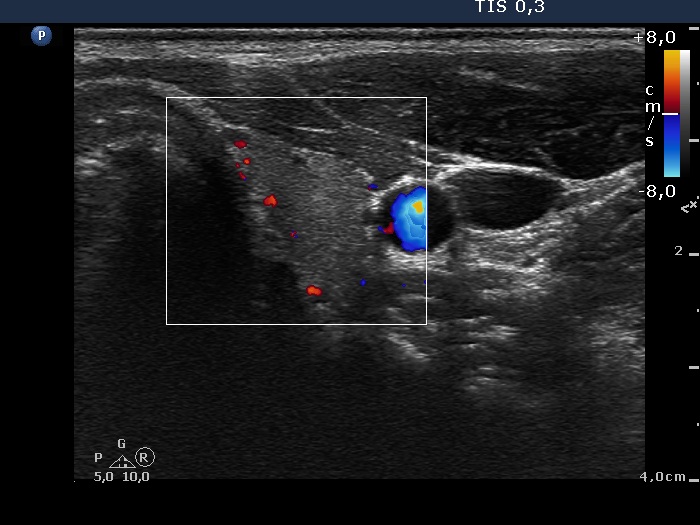

Follow-up examination 11 months later (3rd row of images):

Clinical presentation: The patient had no complaints.

Palpation: no abnormality.

Functional state: euthyroidism with TSH 1.09 mIU/L, and FT4 17.1 pM/L.

Ultrasonography: The thyroid was echonormal with several small minimally hypoechogenic areas. The vascularization was less than the average.